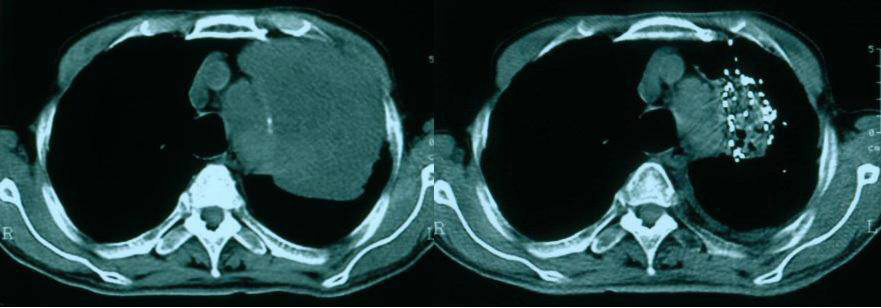

放射性粒子植入治疗技术

粒子植入全称为“放射性粒子植入治疗技术”,是一种将放射源植入肿瘤内部,让其以摧毁肿瘤的治疗手段,属于放射治疗的一种特殊照射方式,而放射治疗是治疗肿瘤三大手段之一,70%肿瘤病人需作放射治疗。

放射性粒子组织间永远植入治疗肿瘤是指通过影像学引导技术(超声、CT/MRI) 将具有放射性的核素直接植入到肿瘤靶体积内或肿瘤周围,通过放射性核素持续释放射线对肿瘤细胞进行杀伤,达到治疗肿瘤的目的。